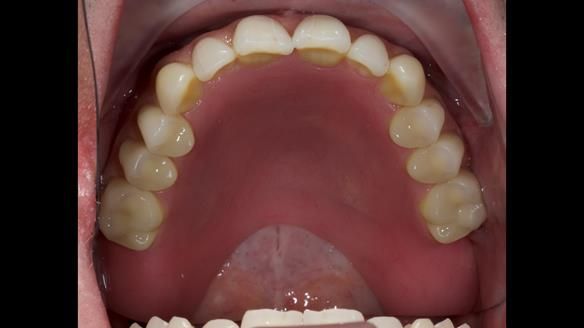

3. Both upper and lower dentures can be enhanced in appearance.

The detailed clinical situation and treatment process are outlined below, with clinical work provided by me and technical work by Rowan Garstang. New complete implant supported complete dentures were made. The new upper denture had ‘almost’ full palatal extension for the non-splinted implants following ITI guidelines. A decision was reached to retain the worn Kerator attachments, as their removal could potentially accelerate implant failure. The treatment spanned five visits for denture fitting and one review. Alisdair expressed great satisfaction with the treatment, noting a significant enhancement in his overall quality of life.